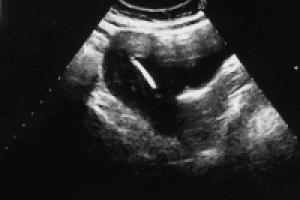

Normal livmoder

Normal livmoder m. spiral